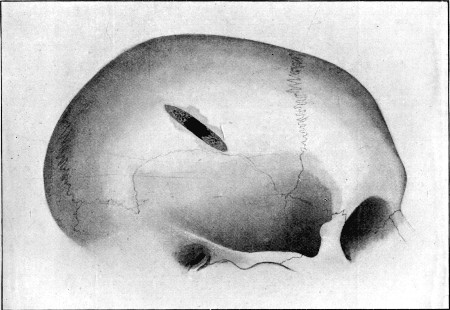

CHAPTER III

GENERAL CHARACTERS OF WOUNDS INFLICTED BY BULLETS OF SMALL CALIBRE

Type wounds—Nature of external apertures—Direct course of wound

track—Multiple wounds—Small bore and sharp localisation of

tracks—Clinical course—Mode of healing—Suppuration—Wounds of

irregular type—Ricochet—Mauser bullet—Lee-Metford bullet—Expanding

64. Gutter Fracture of First Degree in Parietal Bone 255

65. Diagram of Gutter Fractures 256

66. Gutter Fracture of Second Degree in Parietal Bone 257

67. Diagrams of Gutter Fractures 258

68. Superficial Perforating Fracture of Parietal Region 259

69. Diagram of Superficial Perforating Fracture 260